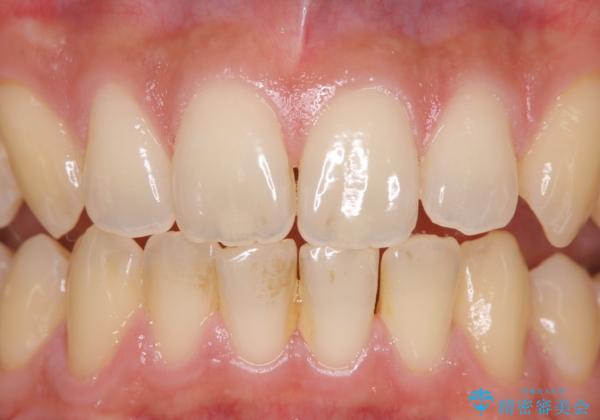

- 数年ぶりに歯科へ来院とのこと。全体的に歯のクリーニングをしてほしいとのことでした。

PMTC60分コースを行いました。

お口のトラブルを予防するには、PMTC(歯科医院で専門的な機械や材料を使用してクリーニング)を定期的に行うことが効果的な治療法です。

PMTCを行うことにより、スッキリと爽快感が得られたり、見た目も清潔感のある状態になるため、今後の治療などお口に対するモチベーションUPにも繋がります。